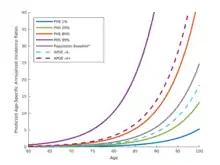

3) Development of the polygenic hazard score (PHS)[14][15] for predicting Alzheimer's disease age of onset, in collaboration with Chun Chieh Fan and Anders Dale.[16][17][18] A commercial version of PHS, which calculates genetic risk for an individual using genomic data from 23andme and Ancestry.com, is available from Dash Genomics.[19]